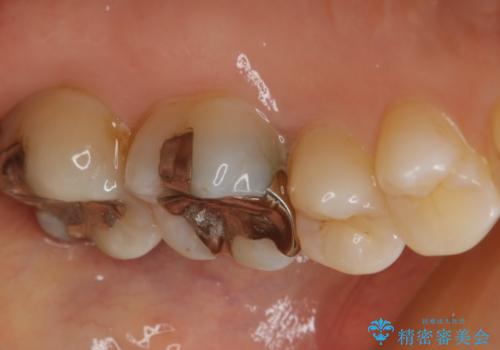

- 左上6番の銀歯をセラミックにしたいと希望され来院された患者様です。

切削量を考慮し、セラミックインレーを選択しました。

銀歯を除去したところ虫歯が深かったので、CRを詰めた上で形態を整えています。